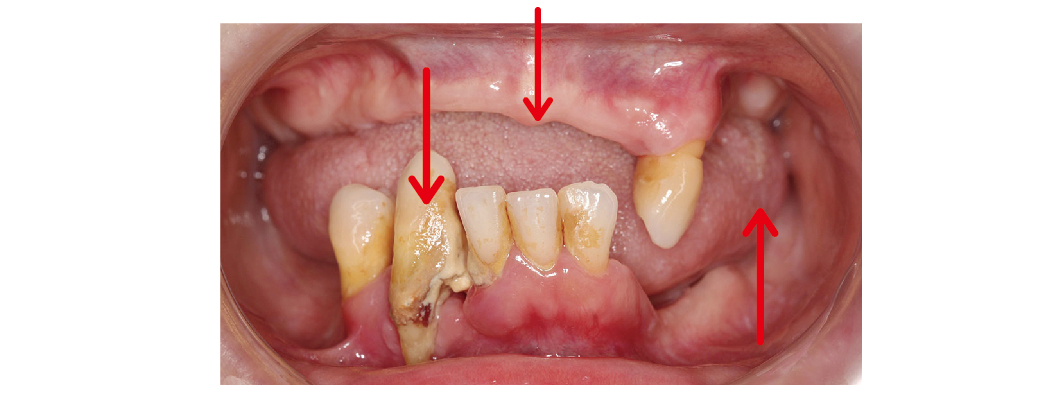

All-on-4/6 全口重建是一個很完整、系統性的治療流程,我們在開始之前,會先幫您做詳細的評估,包括拍攝X光、3D斷層掃描,還有口內外的檢查,來了解目前牙齒、骨頭和牙周的狀況,接下來,我們會根據您的需求和生活習慣,討論最適合您的治療方式。

▲初診的數位口內照可發現,上、下顎嚴重缺牙,下顎門牙牙根外漏,咬合崩壞造成牙齒位移